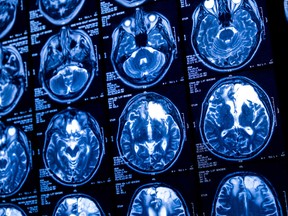

The human mind has 4 distinct turning factors the place its construction modifications, in accordance with a research printed within the journal Nature Communications, demonstrating that mind growth shouldn’t be as linear as you may assume.

In the brand new research, Mousley and colleagues checked out round 4,000 scans from wholesome folks ages 0 to 90 and analyzed their brains. They discovered 4 main occasions when the mind underwent developmental modifications, round ages 9, 32, 66 and 83, dividing the lifespan into 5 distinct phases.